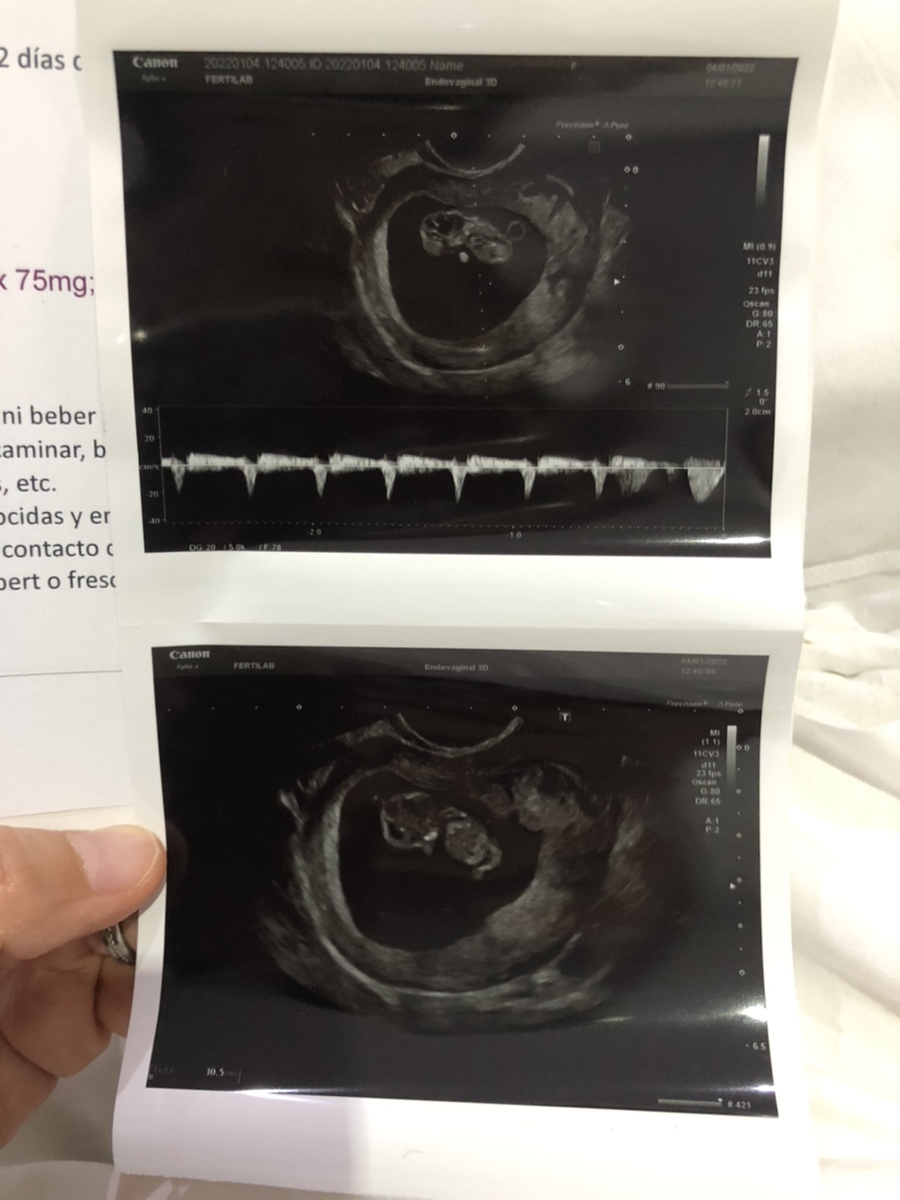

1월 4일 화요일(9주차 4일)

아기크기: 30mm

입덧이 그나마 이전보다 나아져서 아침, 저녁엔 과일을 먹고 점심은 일반식을 먹을 수 있게 되었다. 지난주까지만해도 점심에 일반식을 먹을 수 있을거라고는 상상도 못했는데 큰 발전이다. 사실 잘 먹지 못하고 있는데다가 피부 소양증에 숨 쉬는 것도 힘들어서 아기한테 무슨 문제 있는거 아닌가 노심초사했는데 다행히 아기는 아무문제없이 무럭무럭 자라고 있다. 지난주 수요일에 병원을 방문했을 때는 21mm였는데 일주일 사이에 10mm가 자랐고 팔과 다리도 좀 더 길어진 것 같다. 젤리곰에서 좀 더 사람 같아졌다고나 할까(?) 손가락도 사이 사이가 벌어져 뭔가 진짜 손가락 같아 보였다. 이제서야 점점 실감이 나는 나의 임신 사실…!!!